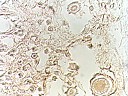

改良银染色法显示表皮中神经纤维的数目:改良银染色法可以观察到,在表皮中,神经纤维的数目也以足底部无毛处穴区最多,背腹部次之,上下肢再次之。

不同穴位的毛发分布:不同部位毛发的分布及表皮的厚度是有差异的。

不同穴区间表皮的神经感受装置有明显的差异性,神经末梢的分布以足底最多,背、腹、上下肢次之;同一穴区针刺后CX43表达增强。 |